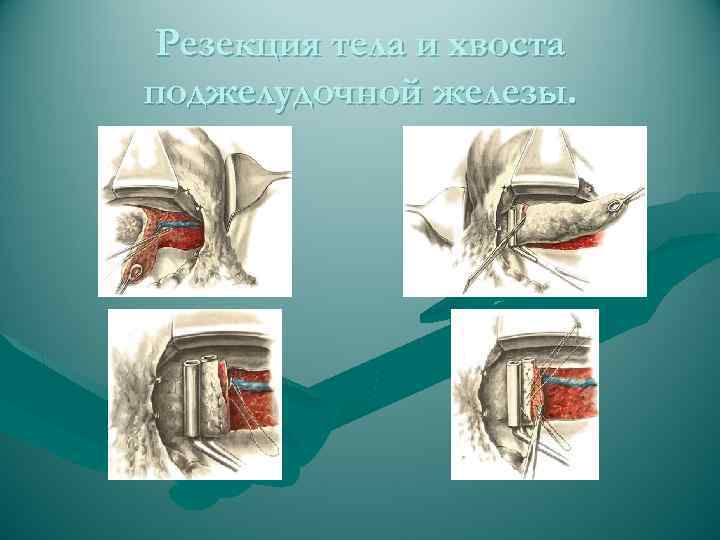

Резекция тела и хвоста поджелудочной железы.

Резекция тела и хвоста поджелудочной железы.